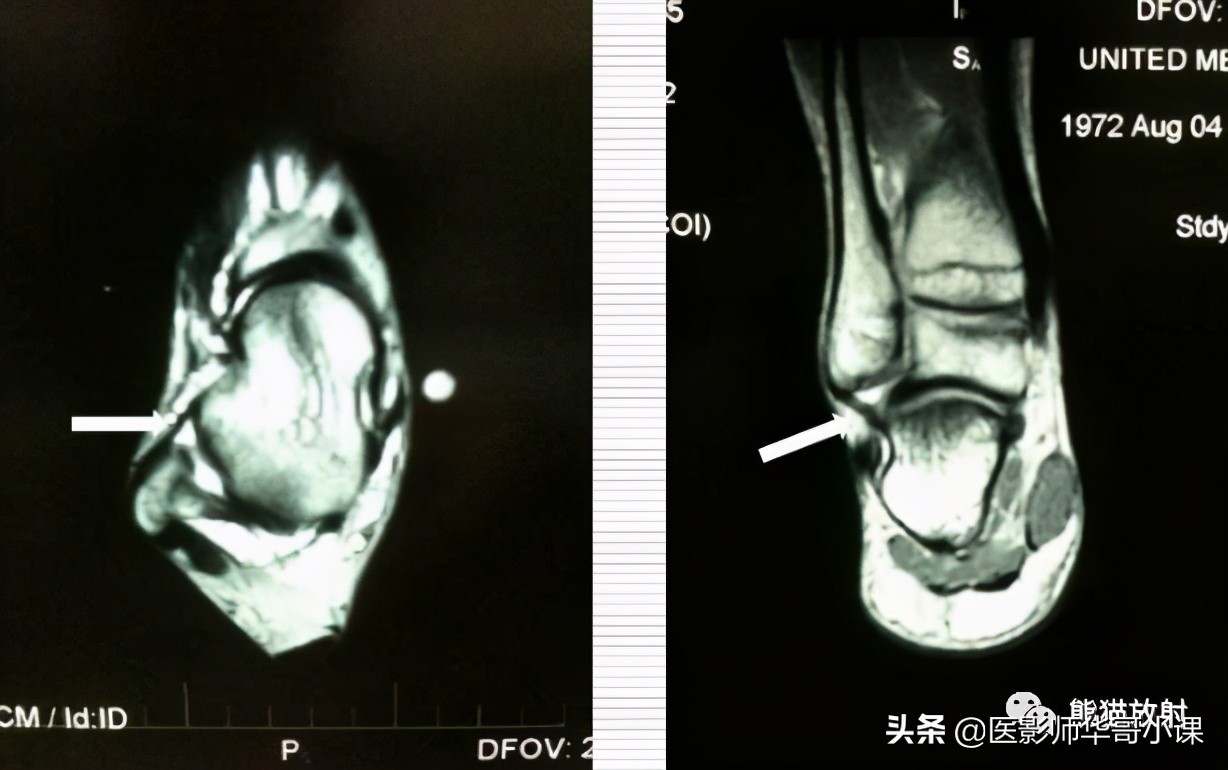

↓ 距腓前韧带:正常及撕裂